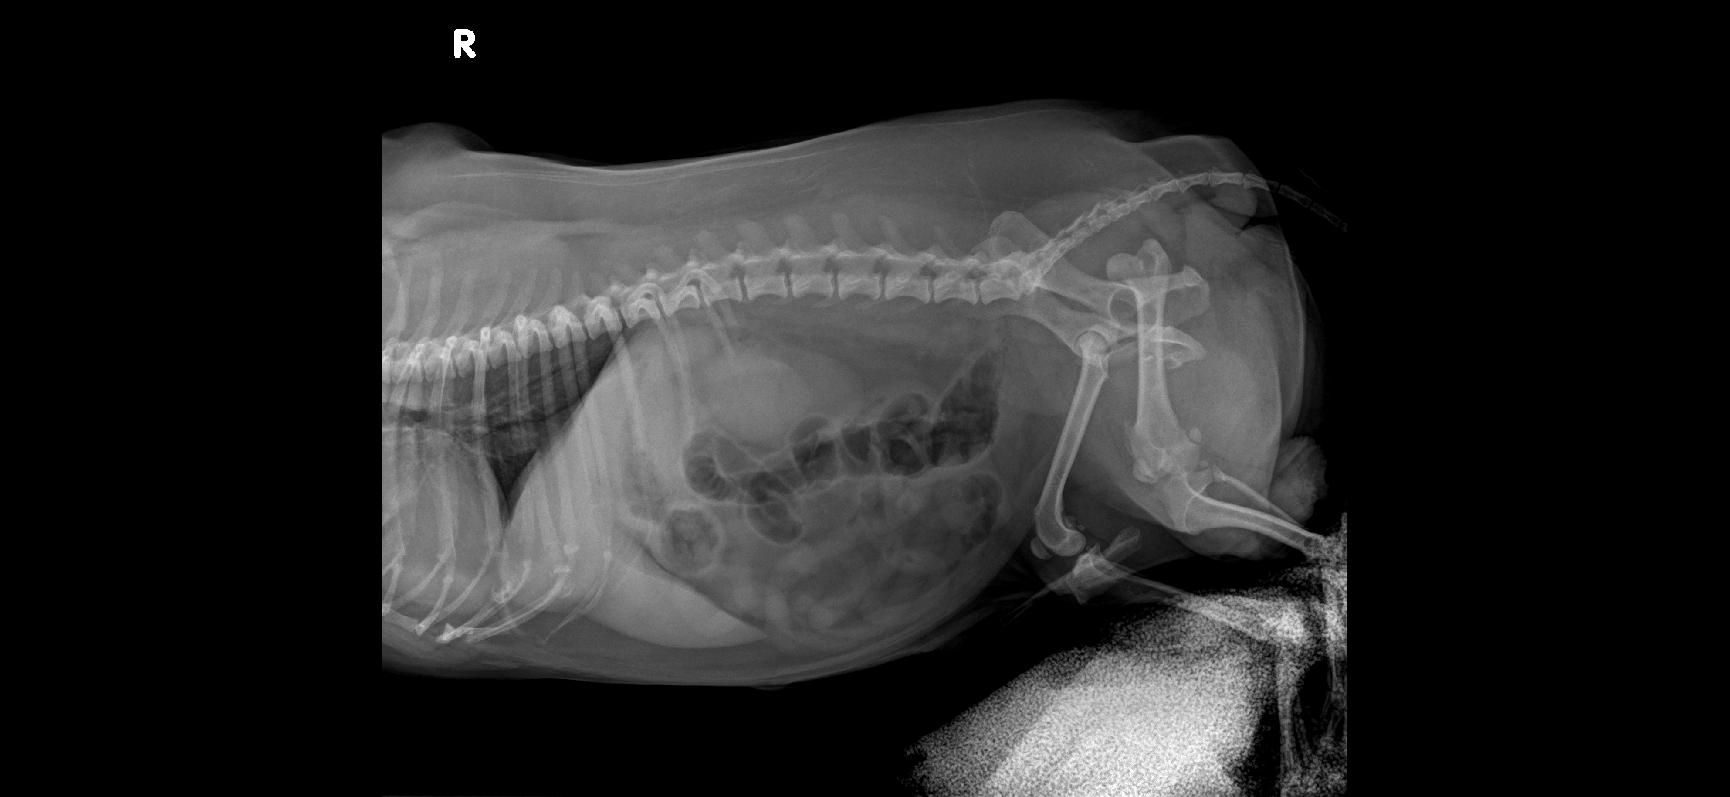

Jsem maminka samoživitelka a před pár dny se nám stalo něco, co si nikdo nepřeje – našeho pejska srazilo auto. Od té chvíle se nemůže postavit na nohy a je odkázaný na mou pomoc.

Veterináři doporučili akutní operaci zadní části těla a několik vyšetření, aby měl šanci znovu chodit a žít plnohodnotný život.